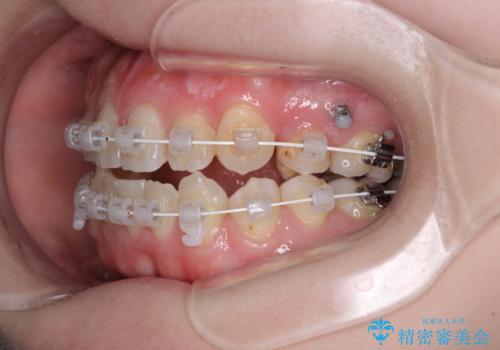

- 矯正装置

- 審美装置

- 左上の八重歯と前歯のデコボコを気にして来院された患者様です。

下顎が左側にズレており、下顎前歯は1歯欠損していたため、左上小臼歯1本を抜歯し、ワイヤー装置にて矯正治療を行うこととしました。

骨格のズレと歯の欠損があったため、仕上がりの調整に時間がかかると思いましたが、舌突出癖の改善や顎間ゴムの装着をしっかりと行ってくださったので、速やかに治療を終えることができました。